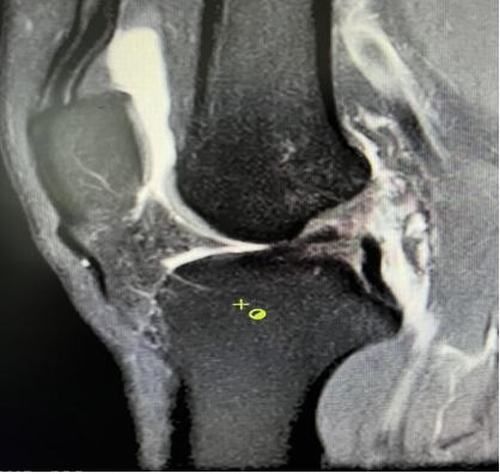

術后X線片

術后磁共振

我院骨關節鏡手術創傷小、恢復快,幾位患者分別于術后5-7天好轉出院。患者親身感受膝關節快速康復過程,對科室醫護表示感激,對早日回歸正常的生活、工作及運動狀態充滿信心。